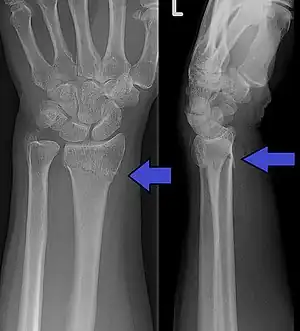

| An X-ray showing a Colles' fracture | |

Diagnosis can be made upon interpretation of anteroposterior and lateral views alone.[6]

The classic Colles fracture has the following characteristics:[7]

- Transverse fracture of the radius

- 2.5 cm (0.98 inches) proximal to the radio-carpal joint

- dorsal displacement and dorsal angulation, together with radial tilt[8]

- Radial shortening

- Loss of ulnar inclination≤

- Radial angulation of the wrist

- Comminution at the fracture site

- Associated fracture of the ulnar styloid process in more than 60% of cases.